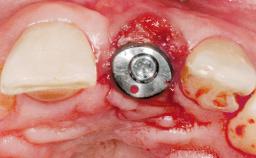

A 29-year-old female patient presented for treatment to replace the upper left central incisor tooth with an implant- supported restoration. The tooth had been intermittently symptomatic for the previous 12 months. The tooth had originally suffered trauma about 15 years previously. Several endodontic treatments had been performed, including an apicectomy procedure to retain the tooth. The patient was healthy and a non-smoker. She had reasonable expectations in regard to esthetic outcomes and the risk of marginal tissue recession following treatment. At medium smile, the gingival margins of the upper teeth were visible, with a display of 3 to 4 mm of the gingival margins. Gingival recession of tooth 21 and a discrepancy in the gingival levels between teeth 11 and 21 was observable during normal speech and smile.

Type of Implants One-Piece

Placement Protocol Immediate implant placement

Tooth Site Maxillary incisor or canine

Socket Morphology Single-root socket